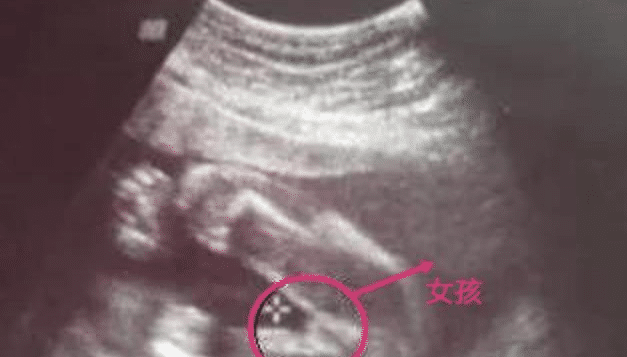

图一 ↓请看下面如何分辨胎儿性别图片7

男孩b超图女孩

男孩女孩b超图片

女胎儿b超图片

b超男孩女孩的区别图